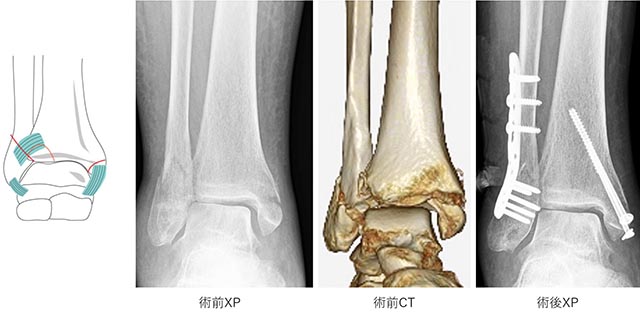

手術の方法は、骨折した部分をもともとの形に整復し、プレートやスクリュー、針金などを用いて固定します(図6−8)。

図7.TypeB骨折